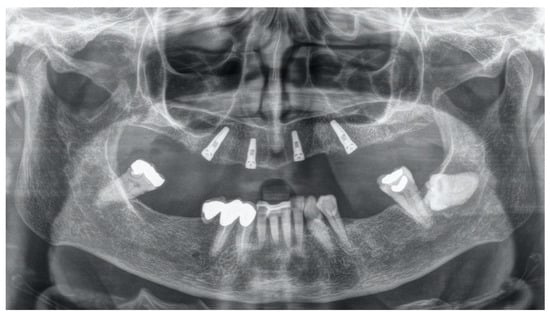

Angled Screwdriver Solutions and Low-Profile Attachments in Full Arch Rehabilitation with Divergent Implants

2. Report and Protocol